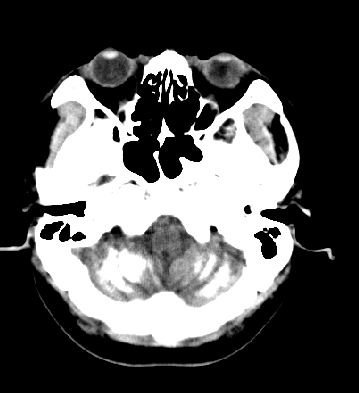

女性 38岁 病人脚弓反张 8岁以后不能行走 今年查pth11.9ng/ml(正常28ng/ml)

谢分享----甲状旁腺功能减退

这么弥漫的钙化还第一次见。

考虑甲状旁腺功能减退症,该病是因甲状旁腺激素分泌减少或功能障碍所引起的少见病。其特点是低血钙,高血磷,且血pth极低。因低钙常可引起神经精神激惹症状,包括手指,趾,口角麻木,严重时可出现肌肉痉挛,喉哮鸣和惊厥,甚至癫痫样发作,有的可出现抑郁症及精神失常。长期的高磷血症可引起脑内结构对称性多发性钙化,特别是小脑和基底节的钙化可致锥体外系症状,而钙化的ct表现为类似于脑出血的密度增高影。

原发性甲状旁腺功能减退症和fahr病都有神志上的改变等症状,且头颅ct检查均可见颅内出现钙化。但fahr病无pth低下,ct表现钙化影在大脑半卵圆中心皮髓质交界处、丘脑、小脑齿状核等处。 而甲状旁腺功能减退症pth极低,ct虽可见钙化影,但部位在小脑和基底节等处。